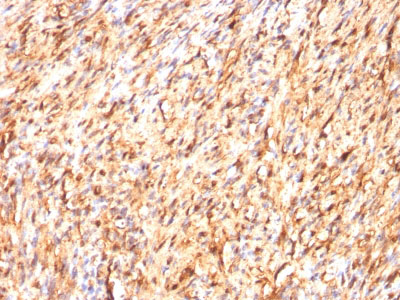

Formalin-fixed, paraffin-embedded human Melanoma stained with S100A1 Monoclonal Antibody (S100A1/1012).

Formalin-fixed, paraffin-embedded human Schwanoma stained with S100A1 Monoclonal Antibody (S100A1/1012).